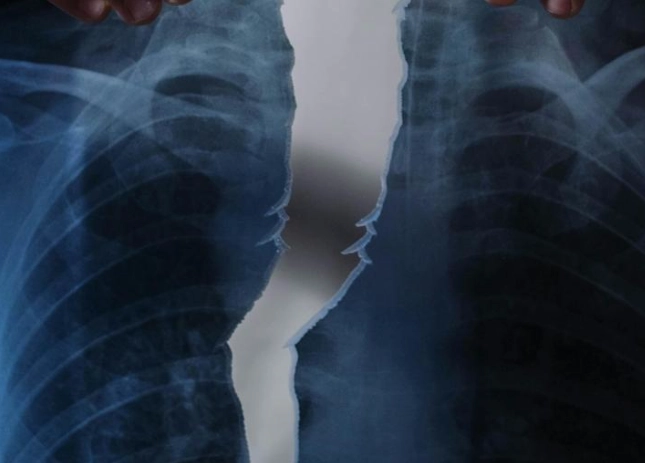

肋骨骨折後,身體會啟動自然的愈合過程,包括炎症期、修復期和重塑期。這段期間,營養攝取直接影響骨骼的再生能力。如果吃了不該吃的東西,可能會干擾這些階段,導致恢復延遲或併發症。例如,高鹽分食物會引起水腫,增加胸腔壓力,讓呼吸都變得更痛苦。而辛辣食物則可能刺激神經,加劇疼痛感。

有些研究指出,飲食控制能減少併發症風險,比如肺炎或感染。肋骨骨折常伴隨呼吸困難,如果飲食不當導致腹脹或炎症,可能會讓呼吸更吃力。這點我深有體會,當初因為貪吃鹹酥雞,結果水腫搞得我連深呼吸都痛,真是自作自受。